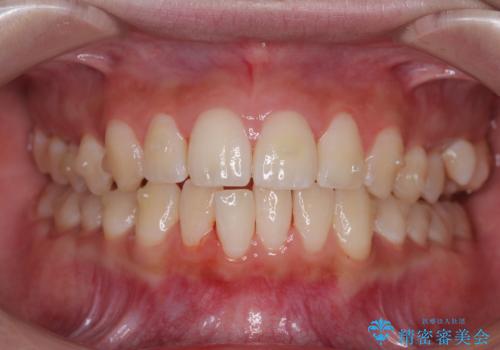

目立たないマウスピース矯正で下の前歯のデコボコをスッキリ解消!たった1年で整った歯並びに

- 今回は「下の前歯のデコボコを治したい」と来院された患者様の症例をご紹介します。

診察してみると、下の前歯が並ぶためのスペースが足りないことが、歯並びがデコボコしている原因でした。

この計画により、デコボコだった下の前歯はしっかりと並び、わずか1年で治療を終えることができました